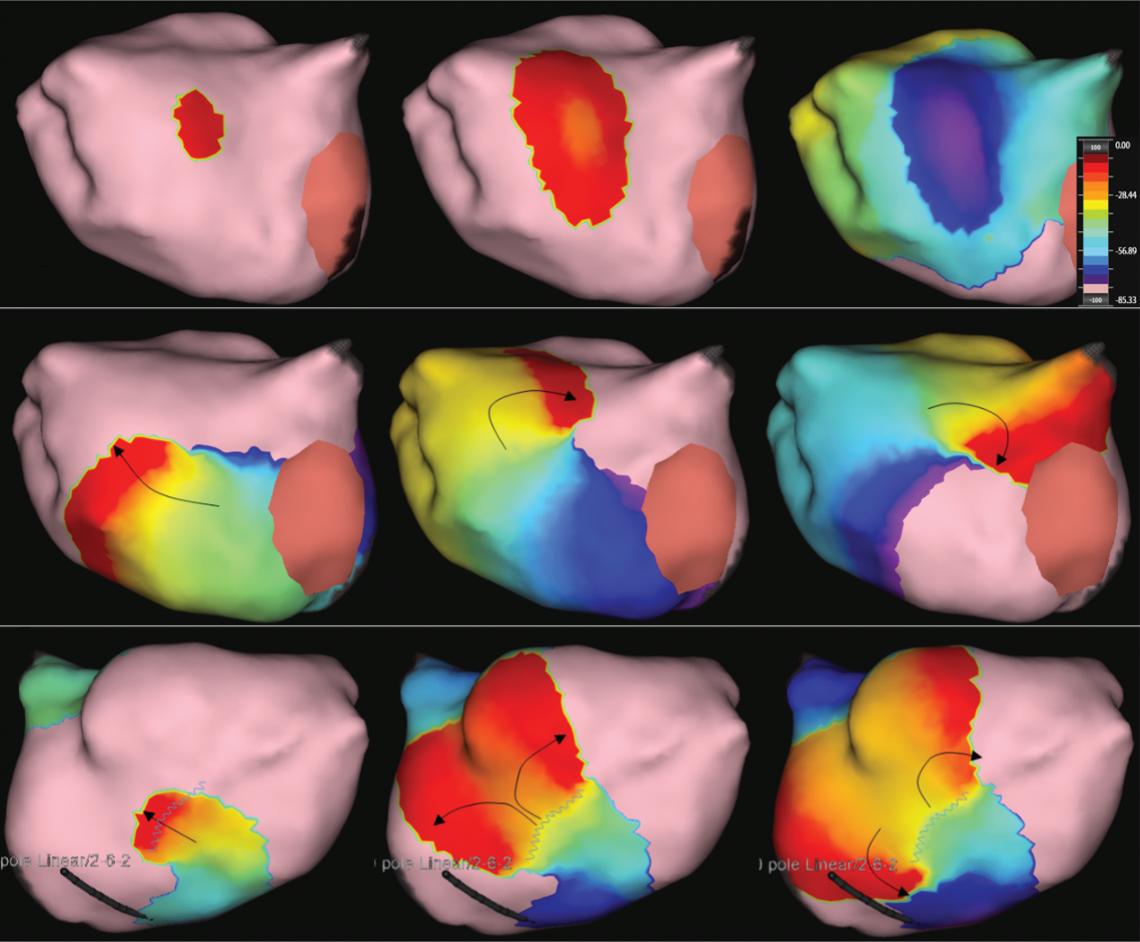

Figure 1: Ablation-induced Late Gadolinium Enhancement After Pulmonary Vein Isolation

Preprocedural LGE-MRI (1 day before PVI) Post-ablation LGE-MRI (3 months after PVI) LIPV RIPV LSPV RSPV LIPV RIPV LSPV RSPV Postero-anterior view Postero-anterior view

Left: 3D reconstruction of the LA with colour-coding based on image intensity ratios with thresholds for dense scar (red >1.32) and border zone (yellow 1.2–1.32), using ADAS 3D software (Adas3D Medical). Blue lines indicate the plane of the LA slices on the right. Middle: Overlay of the T1-weighted images with the LGE colour-coding described above. White arrows point to local ablation-induced LGE lesions. Right: T1-weighted LGE-MRI slice depicting the LA with evident LGE of PV ostial walls. LA = left atrium; LAA = left atrial appendage; LGE = late gadolinium enhancement; LIPV = left inferior pulmonary vein; LSPV = left superior pulmonary vein; PV = pulmonary vein; PVI = pulmonary vein isolation; RIPV = right inferior pulmonary vein; RSPV = right superior pulmonary vein.

Figure 2: Gaps in Ablation Lesions After Pulmonary Vein Isolation

Examples of discontinuations of ablation-induced LGE lesions encircling the right (A) and left pulmonary veins (B), respectively, in a patient with AF recurrence after PVI. Left: 3D reconstruction of the LA with colour-coding based on image intensity ratios with thresholds for dense scar (red >1.32) and border zone (yellow 1.2–1.32), using ADAS 3D software). White arrows indicate local gaps. Pink lines indicate the plane of the left atrial LGE-MRI slices on the right; Middle: Overlay of the T1-weighted left atrial slices with the LGE colour-coding described above. White arrows indicate local gaps corresponding to the ones indicated in the 3D reconstructions on the left; Right: T1-weighted LGE-MRI slices without colour-coding. LA = left atrium; LAA = left atrial appendage; LGE = late gadolinium enhancement; LIPV = left inferior pulmonary vein; LSPV = left superior pulmonary vein; PV = pulmonary vein; PVI = pulmonary vein isolation; RPV = right pulmonary vein; RIPV = right inferior pulmonary vein; RSPV = right superior pulmonary vein.

Preprocedural LGE-MRI (1 day before PVI) A B Post-ablation LGE-MRI (3 months after PVI) Preprocedural LGE-MRI (1 day before PVI) Post-ablation LGE-MRI (3 months after PVI) LIPV LAA RIPV LSPV RSPV LIPV LAA Superior view Superior view Superior view Superior view RIPV LSPV RSPV LIPV LAA RIPV LSPV RSPV LIPV LAA RIPV LSPV RSPV

Figure 4: Single-touch Late Gadolinium Enhancement-MRI-guided Repeat Pulmonary Vein Isolation

Late gadolinium enhancement (LGE) map (ADAS 3D software) integrated into the 3D mapping system (CARTO 3) for targeted ablation of a single LGE-discontinuity at the right superior pulmonary vein (PV) (right panel) resulting in immediate PV isolation upon radiofrequency application as reflected by the disappearance of the PV electrograms detected by the multipolar mapping catheter (Pentaray, Biosense Webster). Colour-coding of LGE map: Image intensity ratio thresholds for dense scar >1.32 (red) and border zone 1.2–1.32 (yellow).

Figure 5: Recurrent Perimitral Flutter After Two Mitral Isthmus Ablations

Left: Late gadolinium enhancement map of the left atrium (LA) 3 months post mitral isthmus re-ablation (ADAS 3D software). The impulse propagation as determined by electroanatomical mapping (activation mapping with HD grid and EnSite Precision [Abbott Medical]) during the repeat procedure is indicated by yellow arrows. These illustrate how lesions from previous ablations force the wave front to go around the LA roof before meandering back to the mitral isthmus through gaps in the ablation line. Dechannelling by ablating the critical isthmus of slow conduction terminated the tachycardia and rendered it non-inducible. Colour-coding of late gadolinium enhancement map: image intensity ratio thresholds for dense scar >1.32 (red) and border zone 1.2–1.32 (yellow).

Right: LA activation during flutter (mapping with HD grid and EnSite Precision). Yellow arrows indicate impulse propagation. Line of conduction block illustrated by red line.